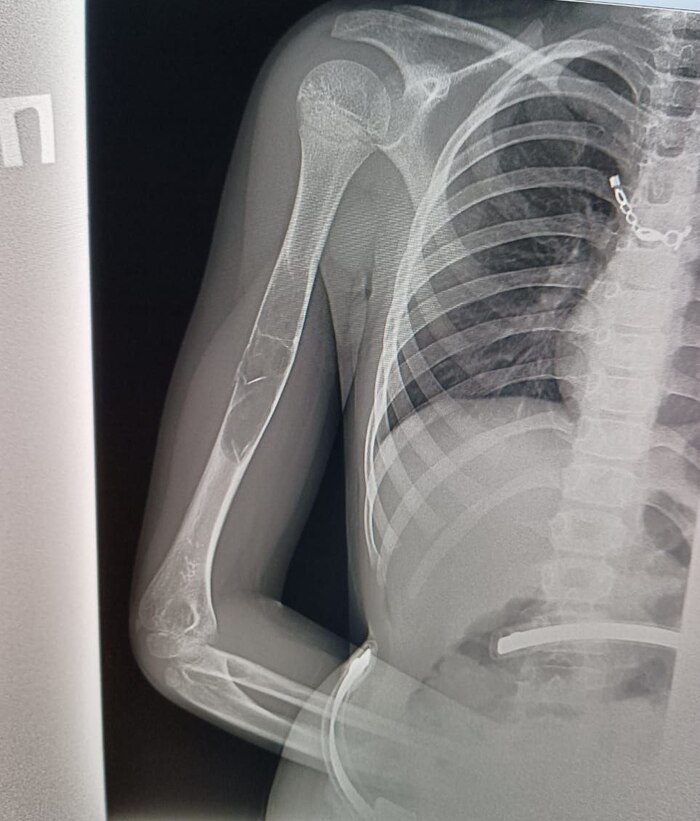

Петербург. Девочка, почти 9 лет, легкий сколиоз. Падение с велосипеда, RG руки, результат

Имеем патологический перелом, причина - предположительно, фиброзная дисплазия или аневризмальная киста кости.

Рекомендованный план лечения: 6 недель в гипсе по турнеру, полное заживление перелома и образование костной мозоли, потом КТ и дифдиагностика, подготовка и операция по удалению всего образования.

Врачи говорят, что зоны роста почти не задеты, есть шанс полного восстановления здоровья и полноценной дальнейшей жизни.

Нужно исключить множественность образований. Соответственно, нужна денсинтометрия или RG всего ребёнка. При ФД наблюдается поражение трубчатых костей: большеберцовой, бедренной, малоберцовой, плечевой, лучевой и локтевой. Из плоских костей чаще страдают кости таза, кости черепа, позвоночник, ребра и лопатка. Нередко выявляется поражение костей кистей и стоп. При АКК наиболее частая локализация: кости позвоночника, затем дистальный отдел бедренной и проксимальные отделы большеберцовой и плечевой костей, кости таза.

Что нужно для 100% исключения более страшных вариантов? Надеюсь, что врачи правы, и сие не злокачественное, но дифдиагностика: Остеофиброзная дисплазия, гигантоклеточная репаративная гранулёма кости, болезнь Педжета, высокодифференцированная центральная остеосаркома, паростальная остеосаркома.